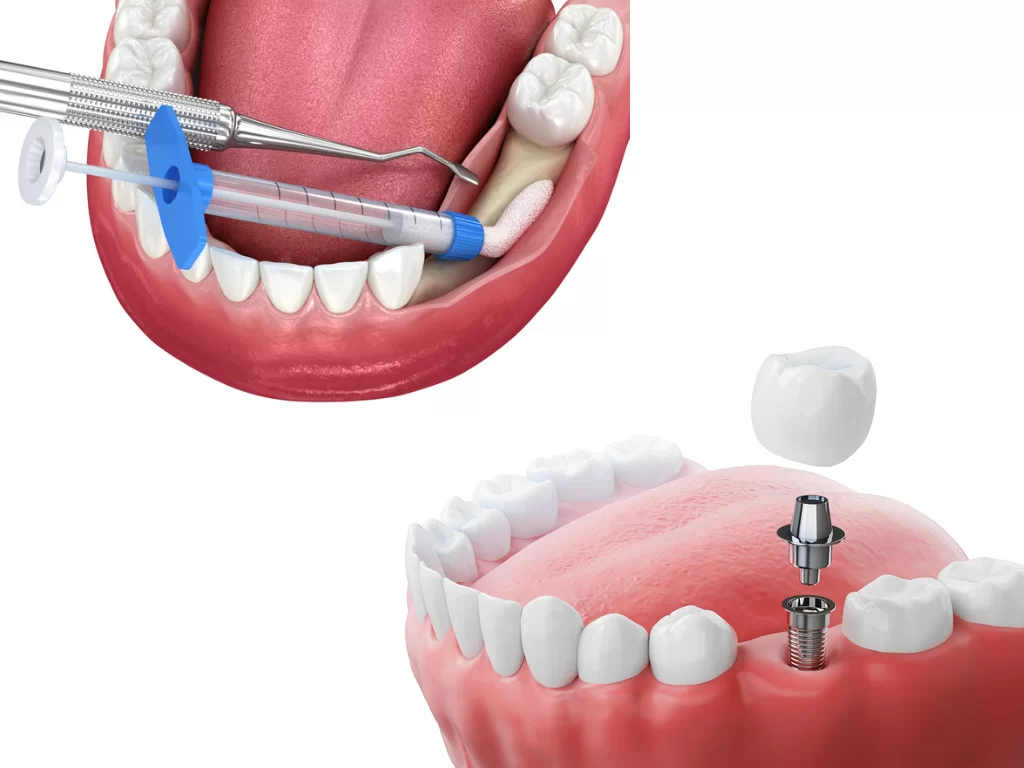

ایمپلنت دندان (Dental Implant) روشی علمی برای جایگزینی دندانهای ازدسترفته است که از یک فیکسچر تیتانیومی (Implant Fixture) بهعنوان ریشه مصنوعی استفاده میکند. این فیکسچر در استخوان فک کاشته شده و پس از جوش خوردن با استخوان (Osseointegration)، روکش دندانی (Crown) روی آن نصب میشود. روشهای مختلف ایمپلنت—سنتی، فوری، پانچ و دیجیتال—هر یک ویژگیها و کاربردهای خاص خود را دارند. در ادامه، هر روش را با جزئیات بررسی میکنیم.

- بیحسی موضعی: ناحیه مورد نظر با بیحسی موضعی کاملاً بیدرد میشود.

- قرار دادن فیکسچر: فیکسچر تیتانیومی در استخوان کاشته و محکم میشود.

- نصب پروتز: اباتمنت (Abutment) و روکش دائمی پس از بهبود نصب میشوند.